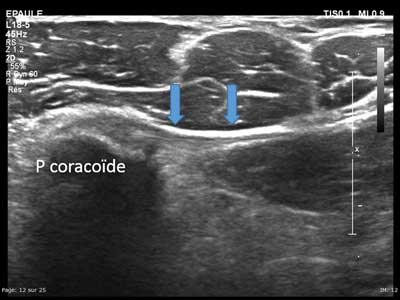

Figure 13

Axial view of the medial part of the coracoid process with enthesis of the pectoralis minor (arrows).